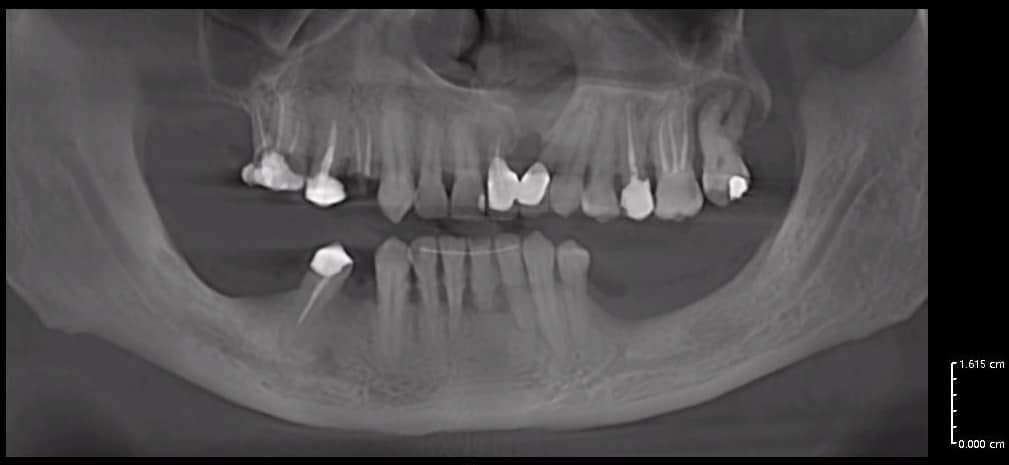

Case of the day where i extracted the 34-35-36 and an immediate placement of 2 implants in the 34-36 sites

sticky bone grafting GTO by osteobiol was used with straumann xenograft

Now healing in